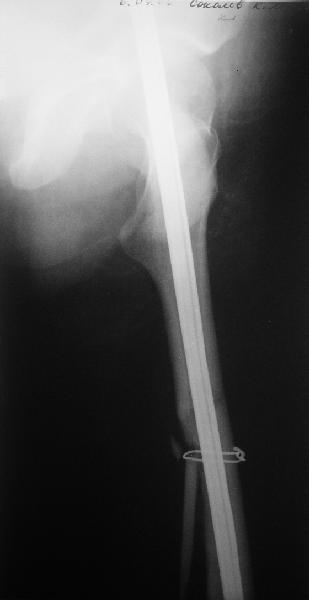

фото несращения бедра

Имя     : фото 2 б.jpe

Имя     : фото 2а.jpe